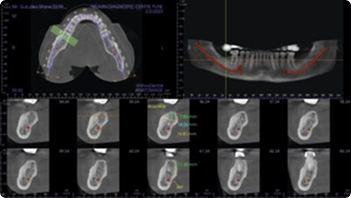

Pre-Implant Assessment

Post-Implant Assessment